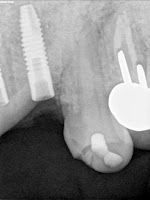

Missing teeth #10 11 shows less radiodense bone with adequate alveolar bone for implants

| Temporary radiopaque restoration in place shows relationship to alveolar bone for esthetic emergence,work-up |